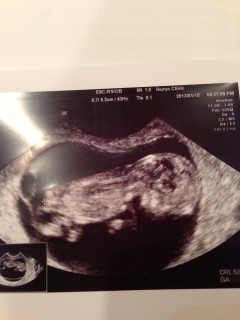

今回の検診でやっと人間の形になってました!

いま5cmぐらいです。

赤ちゃんの大きさは6㎝でした

3ヶ月の検診のときは、そら豆のような形だったのに、たった4週間で手も足も出来て人の形になっていて驚きました。初めて顔が見えてとてもかわいかったです。

背骨などもハッキリと

確認することが出来ました!(^O^)

12w0dで、CLRは5.7ミリ、頭の直径は20ミリです。

12w0d 6cmです。

5.22センチです

頭からお尻までの大きさは45mmとのことでした。